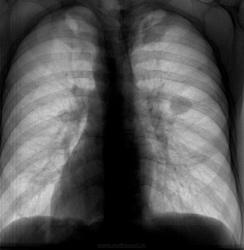

Бомжеватого вида молодой человек, вспомнив о двух детках, решил устроиться на работу, требует положительной флгр. Жалоб не предъявляет, архива нет. Предыдущая Ro-гр.ОГК - 2 года назад в наркодиспансере, где выходил из запоя. По его словам - было все ОК. Что-то есть справа в S1. А что это за гомогенноинтенсивночеткий кругляшок, да еще (если пофантазировать) с дренажным сосудиком? Какая-то киста, или что-то посерьезней. Если допустить, что на верхушке фиброзноочаговые изм., а второе - киста - можно и отпустить с богом. Все равно (по его словам) денег на КТ ОГК, консультации (особенно в онко) нет. Пожалеть деток?

Не внушает мне эта тень «фейсно», как отражение периферического рака, никакого доверия и симпатии.